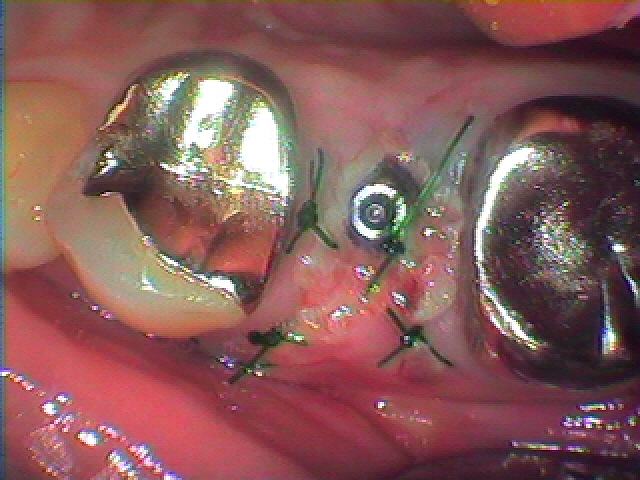

インプラント埋入後の3日目の状態になります

3日目になります